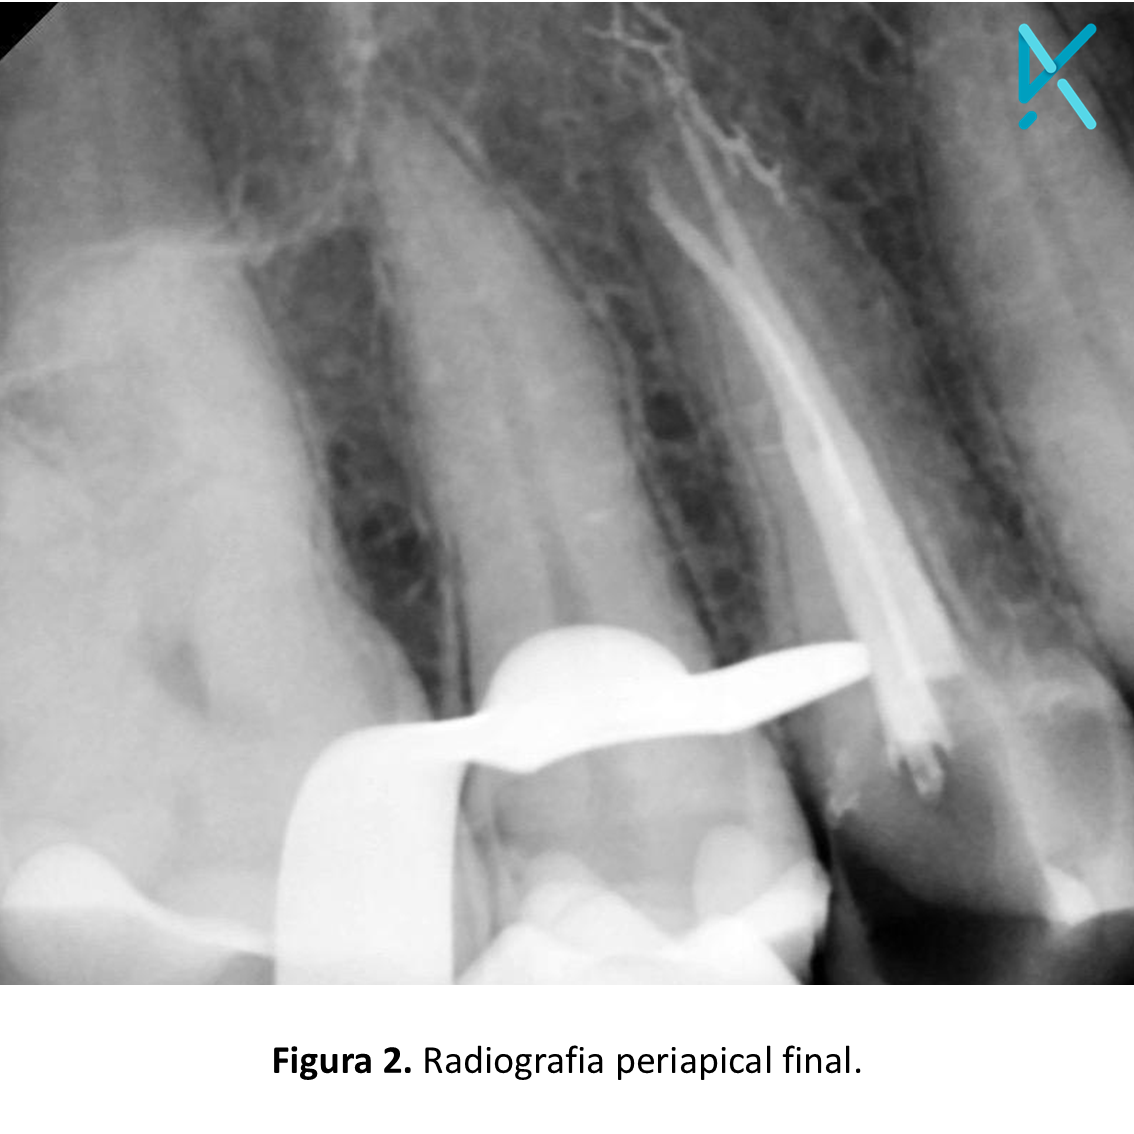

Na radiografia periapical inicial, foi possível observar uma cárie extensa envolvendo as faces distal e oclusal. A endodontia foi realizada em sessão única, e a blindagem da cavidade de acesso, juntamente com a restauração total do elemento, foi realizada com a resina Stela, da SDI, uma vez que a técnica é rápida e de fácil execução.

Estando a cavidade pronta para receber a blindagem endodôntica e o material restaurador definitivo, a resina Stela foi inserida com sua ponta agulhada de auto-mistura, desde a guta-percha até preencher toda a extensão da cavidade, com uma técnica de retroinjeção em uma única aplicação.